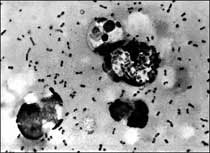

The bubonic plague bacteria taken from a patient. At least eight people have died from an outbreak of bubonic plague in northwestern China but authorities said the disease has been brought under control, state media reported

The bubonic plague bacteria taken from a patient. [AFP]